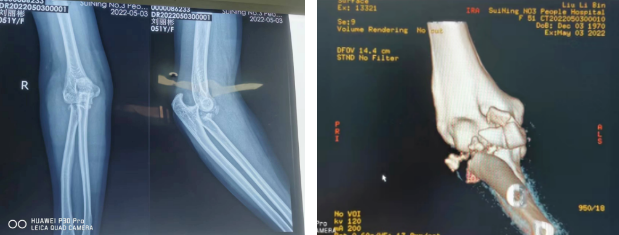

近日,51岁的刘女士不慎摔伤,右肘部损伤严重,外观明显畸形,随即来我院骨伤科就诊,根据CT影像片显示诊断:右侧桡骨头粉碎性骨折、右肘关节脱位。

骨伤科主任医师罗斌为了最大限度地帮助患者改善预后,经科室专家团队讨论,决定为刘女士实施右桡骨头置换手术。

此次手术由骨伤科主任周建全、主任医师罗斌和手术室工作人员共同完成。术后患者患侧肘关节功能及前臂旋转功能改善,恢复很好,患者和家属都非常满意。